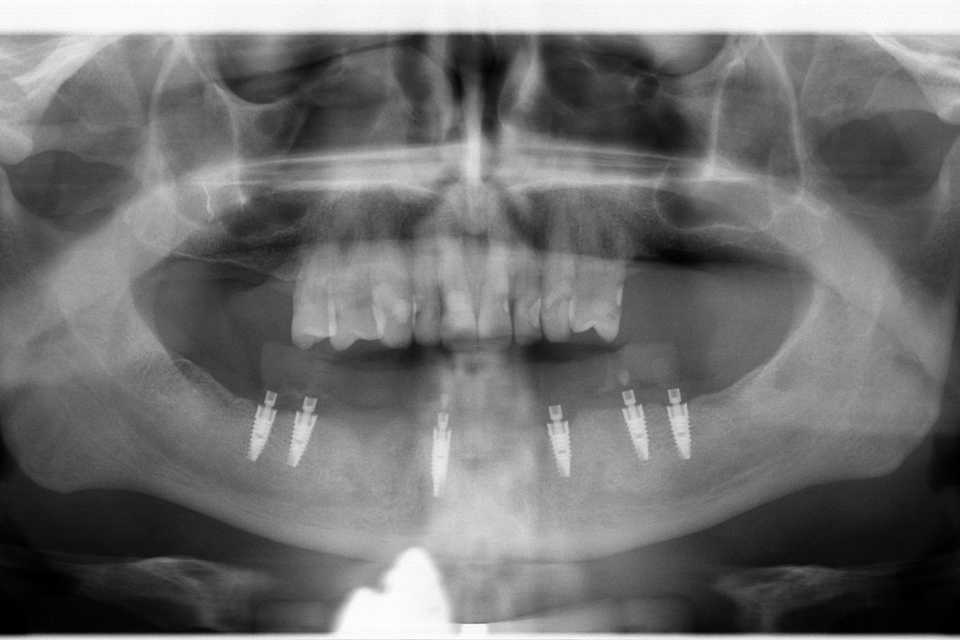

Cazul 64: All on 6

Prima etapă – sub anestezie loco-regională, s-au efectuat extracția dinților parodontotici, chiuretajul și regularizarea crestei osoase, urmate de inserarea a 6 implanturi dentare Paltop (SUA) (preț: 2.500 lei per implant) și realizarea unei lucrări provizorii din acrilat.

A doua etapă – la aproximativ 5 săptămâni de la prima intervenție, implanturile sunt protezate printr-o lucrare fixă, înșurubabilă, din ceramică pe suport de zirconiu (preț: 1.500 lei per element).